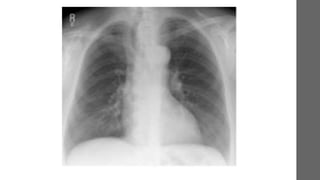

Radiografia de tórax

Espirometria

Bronquiectasias, pneumonia

persistente, sarcoidose e

tuberculose

Radiografia de tóraxMAISCOMUM

• Investigação Radiografia de tórax e espirometria